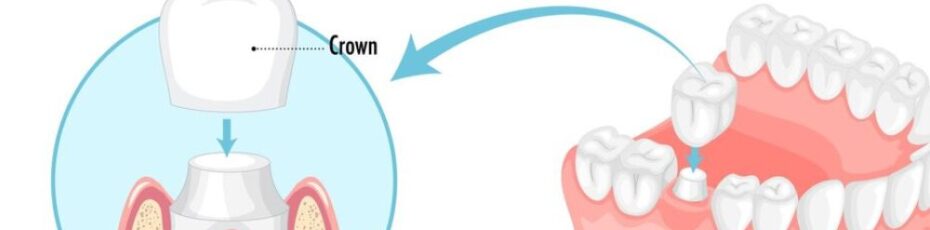

Dealing with a sharp, throbbing ache in your mouth can make it very hard to focus or sleep. When you visit a dentist near you to find a fix, the main goal is to stop the hurting and keep you healthy. While keeping your real teeth is always the first plan, sometimes a tooth is…